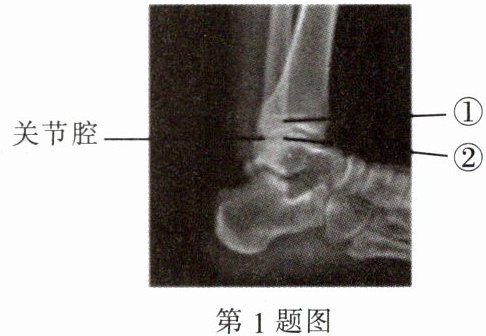

1. (2024·河北)如图为某人左脚的踝关节射线透视图像,其中①②表示踝关节内的结构。下列说法错误的是(

A.①是关节头,②是关节窝

B.①②表面覆盖着关节软骨

C.关节腔内有滑液,使关节灵活

D.踝关节在运动中起枢纽(支点)作用

A